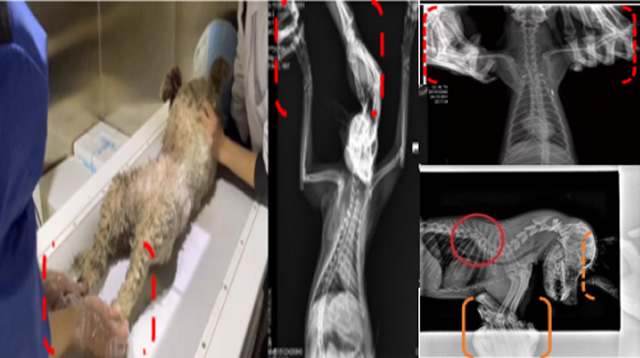

現(xiàn)在寵物醫(yī)療設備得到高速發(fā)展,現(xiàn)在有越來越多的寵物診療機構(gòu)配置X射線裝置如寵物DR。寵物骨折或者有其他疾病不能通過直觀看出來的。寵物診所醫(yī)生都會使用寵物DR來做輔助檢查。但是有時候?qū)櫸镝t(yī)生沒有加強防護,就在寵物DR室給寵物拍X片做檢查。這樣也是會受到X射線的輻射。因為X射線上崗是屬于職業(yè)病危害崗位。長期的輻射會對人體造成一定的危害。寵物醫(yī)生也需要接受X射線照射的上崗前都必須進行放射工作人員的職業(yè)健康體檢。體檢不合格的話是不能擔任放射工作的。未經(jīng)上崗前職業(yè)健康體檢的勞動者從事接觸職業(yè)病危害作業(yè)的行為,已經(jīng)違反了《中華人民共和國職業(yè)病防治法》第三十五條規(guī)定,依據(jù)《中華人民共和國職業(yè)病防治法》第七十五條規(guī)定,需要進行整改罰款。開展寵物放射診療活動,在日常工作中,對本機構(gòu)的X射線危害的職業(yè)病防治,需要知道并做到以下內(nèi)容: